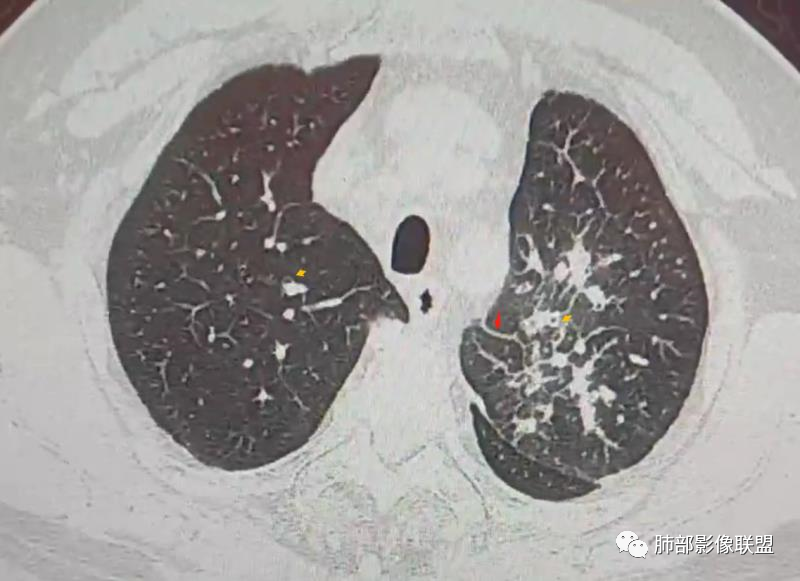

三、影像表现:左肺上叶多发片状高密度影,散在,边缘模糊,支气管壁稍增厚,中轴间质、小叶间隔增厚、有结节感,左肺上叶前段病灶可见胸膜增厚,部分小支气管不能分辨;右肺上叶后段混合磨玻璃结节,边界清,邻近胸膜凹陷;纵膈淋巴结肿大;心包增厚;左侧少量胸水。此外,扫及右侧胸腔内甲状腺肿;左侧肩胛骨旁肌群内脂肪瘤。

四、综合分析:老年男性,以咳嗽咳痰为主要临床表现,无发热,白细胞正常,影像表现为左肺上叶片影,前段结节影、胸膜增厚、部分小支气管不能分辨。左肺上叶中轴间质增厚、小叶间隔增厚、结节感,肺门纵隔见肿大淋巴结,尽管肺部病病灶边缘特征不典型,但高度疑及癌性淋巴管炎这一“次生灾害”却具有相当重要提示意义,而肺癌中最常伴癌淋的就包括腺癌。右肺上叶后段混合磨玻璃结节,边界清楚,张力明显,具有一定特征性,高度指向浸润性腺癌。这对于左肺病灶具有一定程度“助攻”效应。总体而言,本例左肺病灶的诊断关键点在于判断出癌性淋巴管炎。癌性淋巴管炎的结节在外围间质多见,小叶间隔可呈串珠状、结节状增厚,由于出血及水肿,小叶间隔增厚较明显,或呈不规则增厚。有的肺小叶呈多角状阵列。常合并胸水。

图1、2为同一病例,左肺下叶背段周围型肺Ca并左肺下叶局限型PLC,肿块与左下肺门间肺纹理不规则增粗,肿块与膈面有串珠样高密度影相连。图3为乳腺癌化疗后多发转移并弥漫型PLC,双肺多肺叶肺纹理不规则增粗增多并多发微小结节,其中右肺上叶后段肺纹理多呈典型的“毛刷征”,双肺上叶胸膜下区可见多发垂直于胸膜的不规则增厚的小叶间隔及微小结节。图4为右肺上叶周围型肺癌并弥漫型PLC,左肺上叶背段肺纹理不规则增粗增多呈典型的“毛刷征”,右侧叶间胸膜轻度增厚及多发微小结节。图5为胰腺癌术后多发转移并弥漫型PLC,双肺广泛肺纹理增多增粗并多发微小结节,双肺胸膜下多发肺小叶间隔增厚并见微小结节;图6(MPR冠状位)为食管癌术后肺弥漫型PLC,左肺广泛肺纹理不规则增多、增粗及多发小结节,边缘模糊。